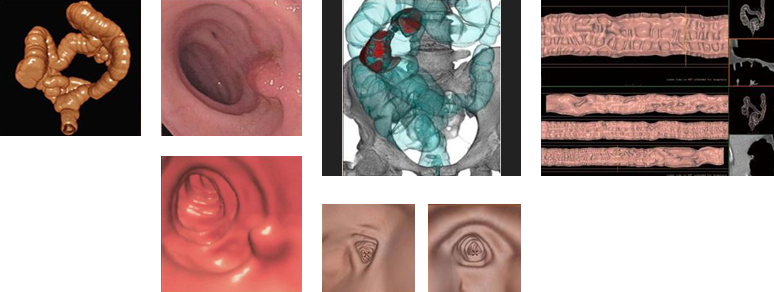

CTコロノグラフィー検査

CTコロノグラフィー検査とは、CTを用いた大腸検査の総称です。拡張や鎮痙剤で腸管の蠕動運動の抑制を行い、注腸X線造影検査や大腸内視鏡と同様の前処置をしたうえで撮影し専用の大腸解析ソフトを用いて、様々な再構成画像を作成し評価します。